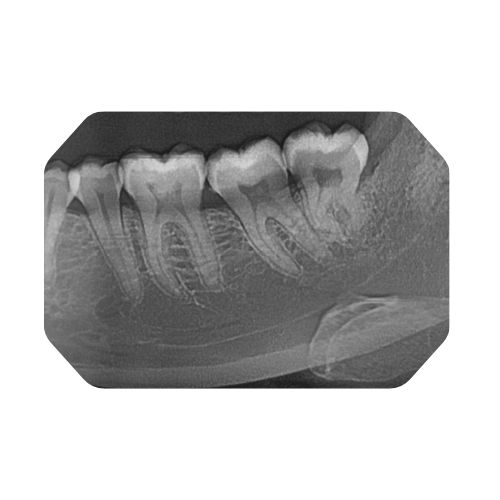

A panoramic dental scan (also known as an OPG or orthopantomogram) provides a broad, single-image view of your entire upper and lower jaws, all the teeth, the jaw joints (TMJ) and surrounding bone structures. It is highly valuable for:

- Assessing wisdom-teeth position, impactions, crowding.

- Planning orthodontic treatments/braces and evaluating tooth development.

- Screening for bone-loss, jaw-joint disorders, cysts or tumours in the maxillofacial region.